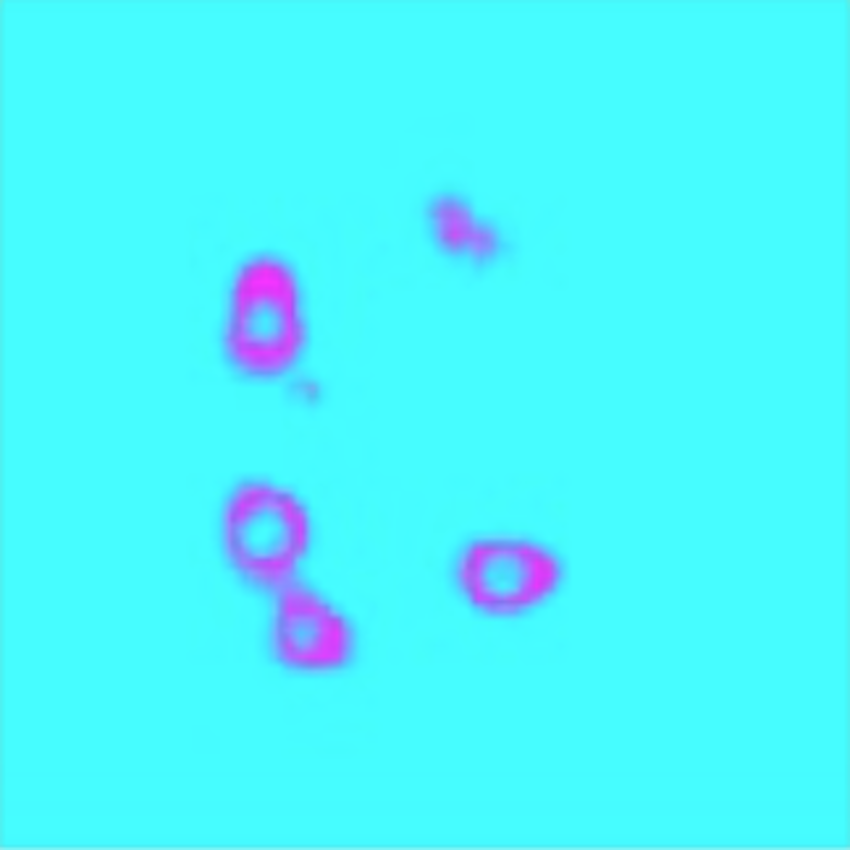

In this paper, we present U-LanD, a novel uncertainty-driven video landmark detection framework. U-LanD is specifically designed to consider the bias in sparsely annotated video data and automatically detect the location of landmarks on the key frames of the video. U-LanD is based on a core observation: a deep Bayesian encoder-decoder network only trained on labelled key frames, shows significantly higher prediction confidence (lower uncertainty) in test time when deployed on key frames vs. non-key frames, as illustrated in Fig 1. U-LanD exploits the test-time predictive uncertainty as an unsupervised guiding signature to detect landmark points on key frames. U-LanD considers several aspects of predictive uncertainty in landmark detection, namely i) contextual quality control based on landmark heatmaps; ii) pixel-level epistemic uncertainty with variational dropout; and iii) pixel-level heteroscedastic aleatoric uncertainty by placing a Gaussian distribution over the observed labels.

To generate the ground-truth masks for training, we place a circle with radius at the coordinates of landmarks, where is a hyperparameter tuned to account for the inter-observer variability in landmark labels. Here for the purpose of demonstration, we adapt a circle formation, while more complex choices of ground-truth genesis based on the underlying object could be investigated [30]. At test time, the center of gravity (COG) of the predicted heatmaps are used to obtain the coordinates of the landmarks. The BU-Net, only trained on key frames, generally produces valid predictions in vicinity of the key frames, and produces invalid predictions for non-key frames, where it shows an unseen event or the object of interest does not have clear visibility. Therefore, the prediction quality based on the interpretation of the heatmaps could be used as a criterion to detect the key frames discussed next.

The predicted heatmaps by the detector are passed through a sanity check to discard non-valid predictions, which correlate to non-key frames. Each key frame has landmark points, where each point is marked in the ground-truth mask with a circle of radius . We perform a spatial sanity check on the predicted heatmap of each frame by locating all blobs with radius ; if heatmaps are located in the prediction, and , the frame is discarded as a non-key frame. The BU-Net predictions tend to be invalid the further you move from the key frames, i.e., the detector fails to predict enough heatmaps () or predicts multitude of noisy heatmaps (). After this initial contextual sanity check based on the prediction heatmap, the remaining candidate key frames are assessed in terms of predictive uncertainty. The two major sources of predictive uncertainty considered are epistemic and aleatoric.

4.5 Epistemic Uncertainty

The epistemic uncertainty accounts for the ignorance in model parameters, which can be decreased by collecting more training data. The BU-Net, having only been trained on key frames, is expected to have a lower epistemic uncertainty on frames that have characteristics similar to the key frames, and higher uncertainty as the further you move from the key frames in time (OOD frames). Therefore, the epistemic uncertainty of BU-Net’s prediction could be used to distinguish between key and non-key frames.

4.6 Aleatoric Uncertainty

The aleatoric uncertainty accounts for the ambiguity in the observed data, such as the inherent noise in the measurements or labels. The Bayesian landmark detector is expected to have a higher aleatoric uncertainty on noisy non-key frames, where the object of interest has low visibility. The aleatoric uncertainty of BU-Net therefore can be used to detect the key frames in time.

| a) Sample Non-key Frame | Epistemic | Aleatoric | |

| b) Sample Key Frame | Epistemic | Aleatoric | |